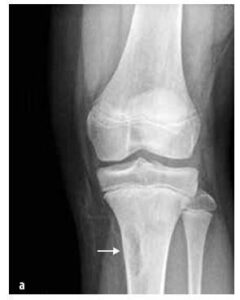

Slika št. 7

Neosificirajoči kostni fibrom